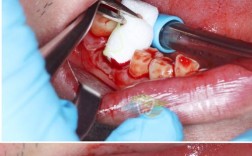

- 补牙(充填): 这是最常见的方法,牙医会清除腐坏的牙体组织,然后用树脂、玻璃离子、银汞合金等材料填充龋洞,恢复牙齿外形和功能。这是阻止蛀牙恶化、避免牙齿最终被拔除或崩解的关键步骤。

- 根管治疗(牙髓治疗): 如果蛀洞深及牙髓,引起牙髓炎或根尖周炎,需要清除感染的牙髓,进行根管消毒、填充,最后做牙冠保护牙齿,这是保住牙齿的最后机会。